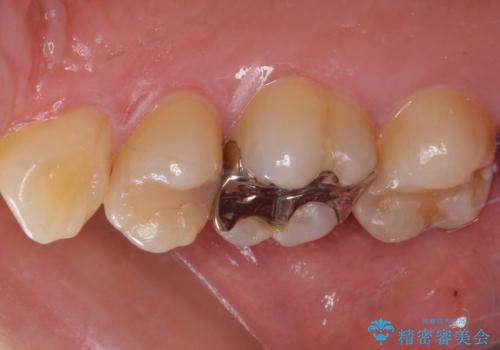

- 奥歯がしみて激痛が続くとのことで来院された患者様です。

診査の結果、不適合な銀歯の隙間からむし歯が進行しており、更には頬側、口蓋側ともに歯肉縁付近に強い知覚過敏症状が認められました。

健全歯質が多いため、インレーおよびむし歯を除去した上で知覚過敏を緩和させる処置を行うことが望ましいと判断されましたが、知覚過敏の症状が一向に改善されないため、全体をセラミッククラウンで補綴することとしました。